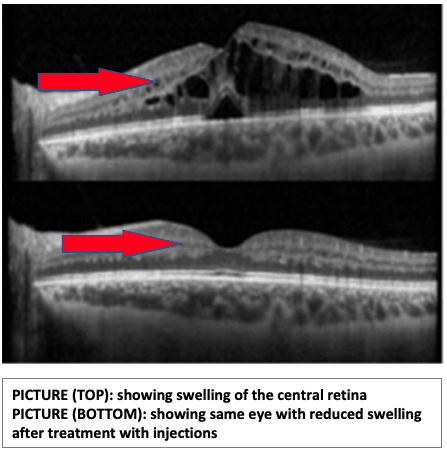

The macular (central part of the retina) can also become swollen due to this blockage and cause distortion in central vision.

In some cases, CRVO may cause swelling in the macular (central part of the retina) called macular oedema. In such cases, medication injections in the eye called anti-VEGF injections may be recommended. Occasionally, steroid injections may also be used.